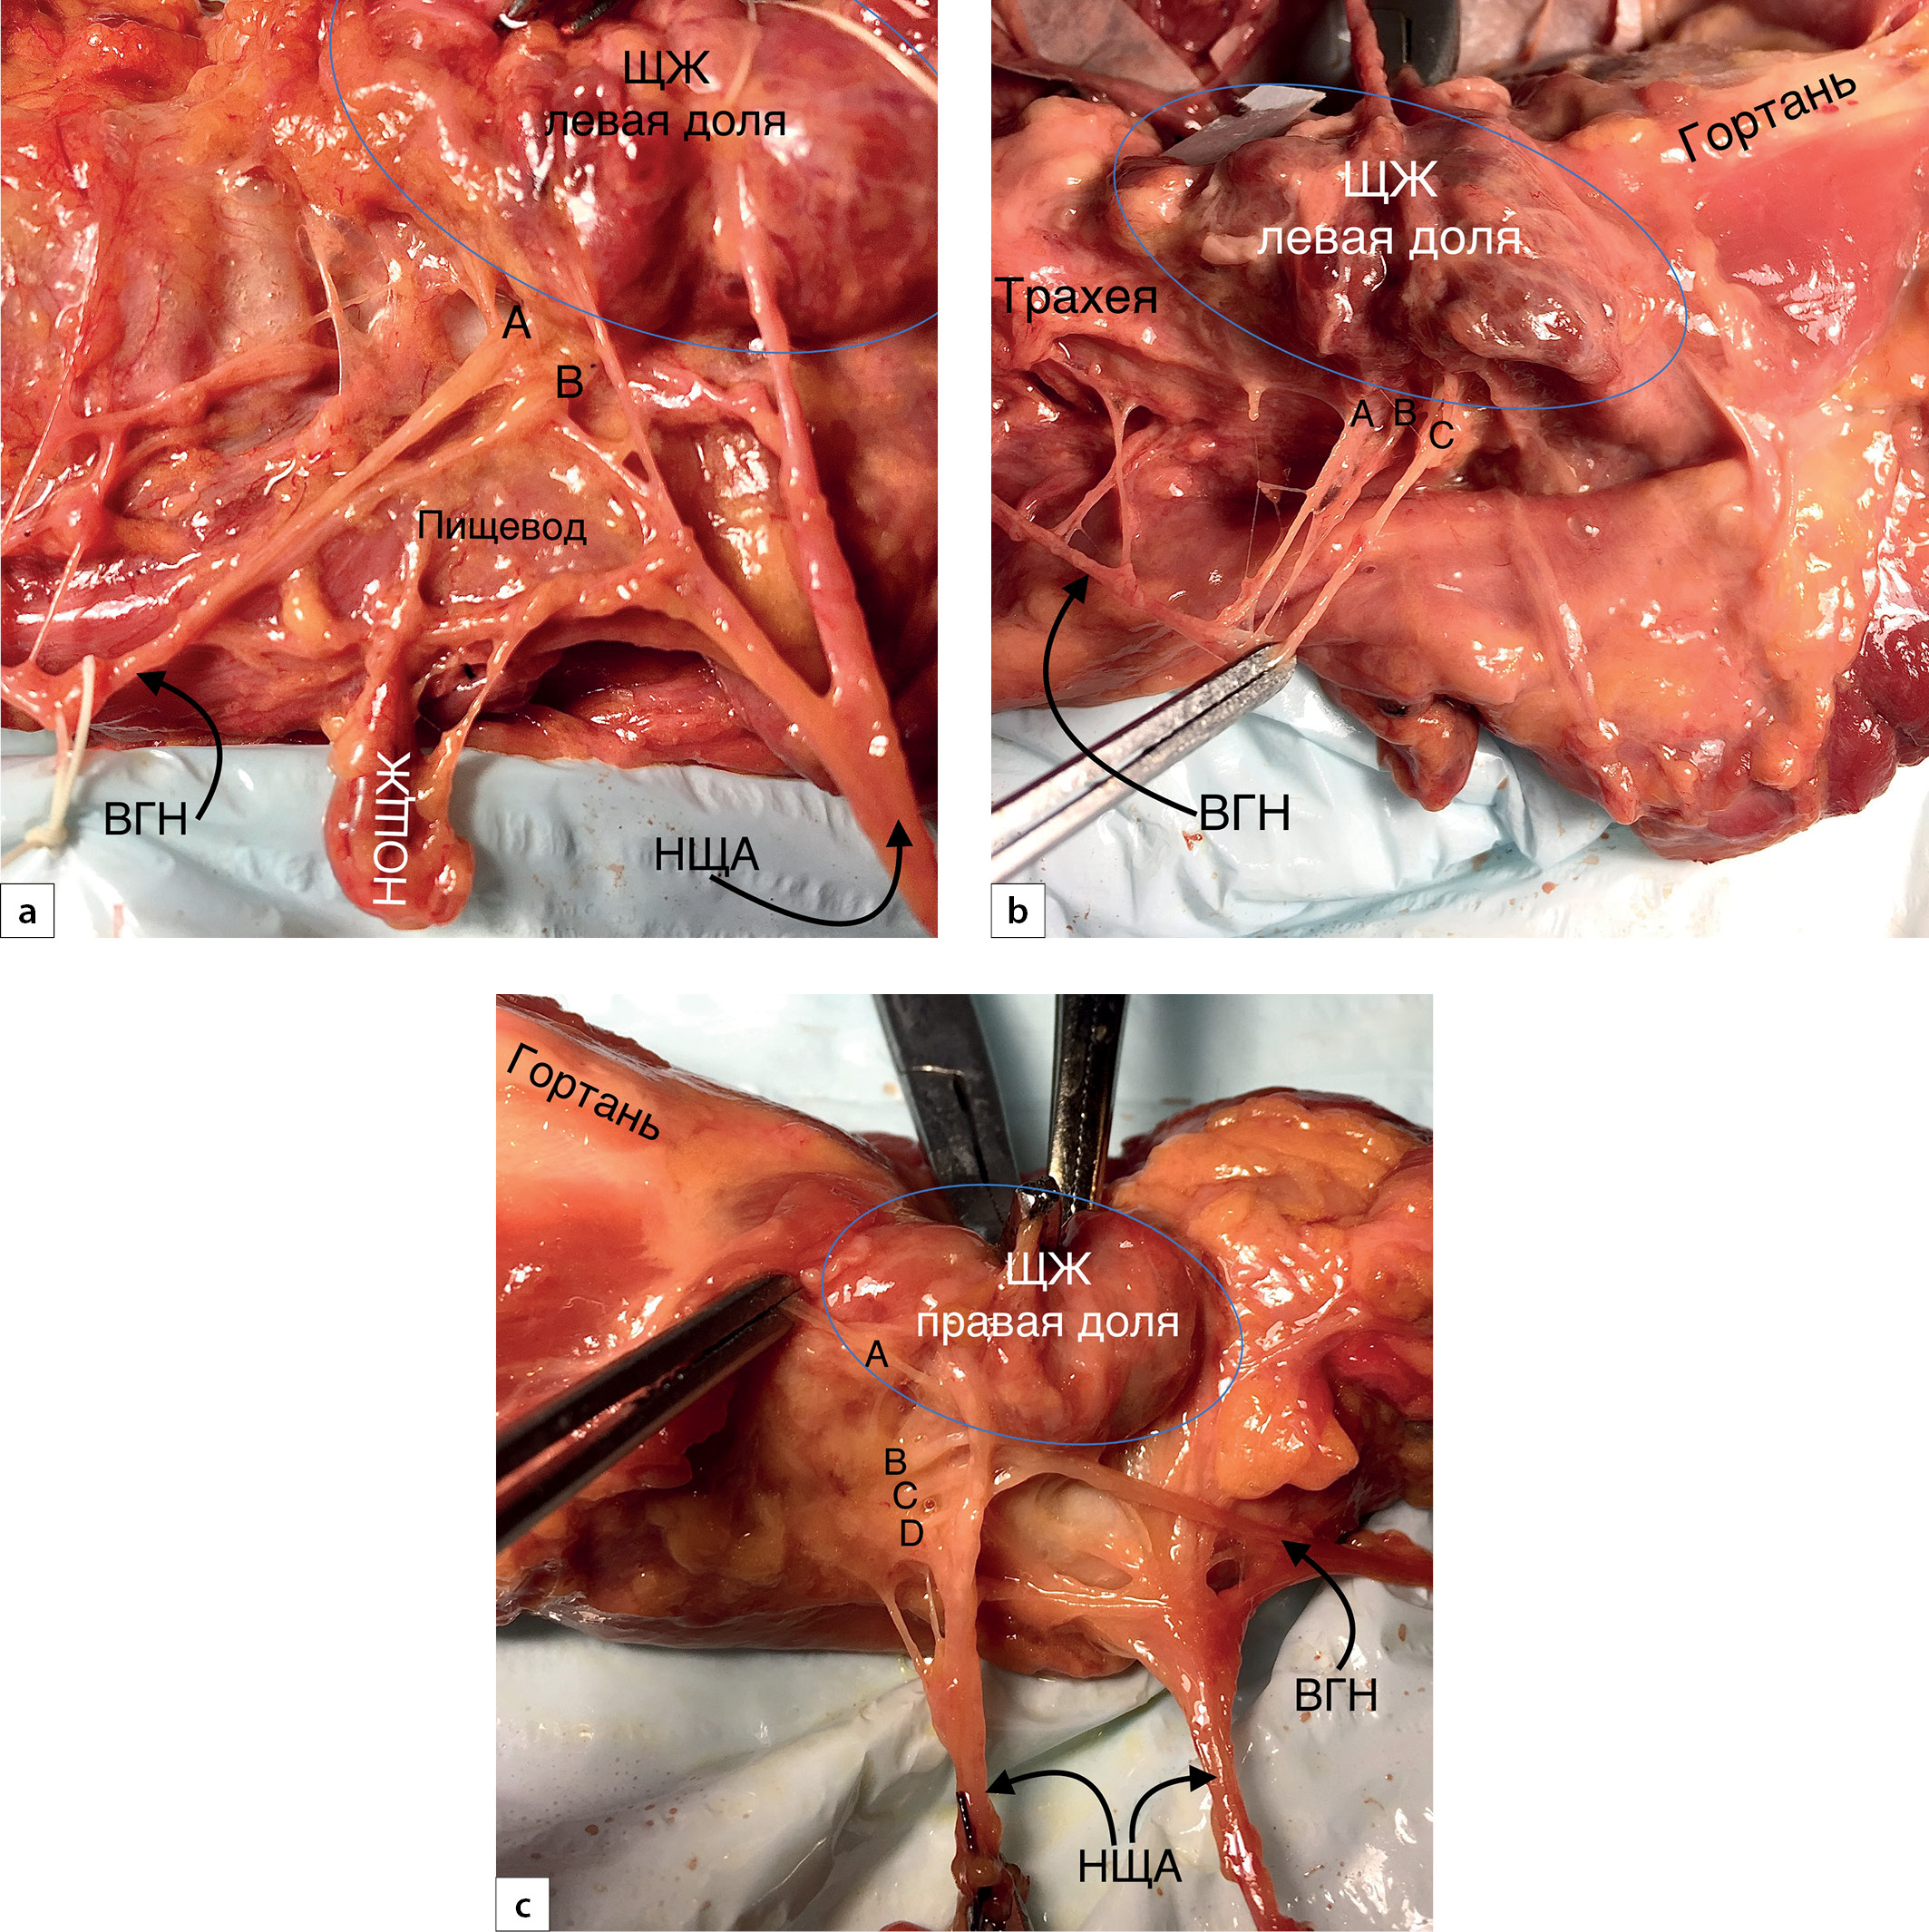

Рис. 3. Гортанные ветви возвратного гортанного нерва (ВГН).

a — две гортанных ветви; b — три гортанных ветви; c — четыре гортанных ветви. А, B, C, D — гортанные ветви. НОЩЖ — нижняя околощитовидная железа.

Аберрантные варианты возвратного гортанного нерва

А) Аберрантные ветви ВГН.

В 13 (28,3%) случаях выявлены дополнительные ветки от наружной ветви ВГН, направляющиеся непосредственно в область «входа» ВГН в гортань. Из них в 2 (4,4%) наблюдениях между нервами визуализирован прямой экстраларингеальный анастомоз (рис. 10).

В 3 (6,5%) случаях выявлены дополнительные латеральные ветви ВГН. Однако проследить их ход на всем протяжении не представлялось возможным (препарат ограничен II фасциальным листком шеи) (рис. 11а). В 1 (2,2%) случае выявлен «обходной» анастомоз между блуждающим нервом и ВГН (рис. 11b).

Рис. 10. Аберрантные ветви возвратного гортанного нерва (ВГН).

a, b — анастомоз между ВГН и наружной ветвью верхнего гортанного нерва (указаны тонкими прямыми стрелками).

Рис. 11. Аберрантные ветви возвратного гортанного нерва (ВГН).

a — две дополнительные латеральные ветви ВГН (отмечены тонкими прямыми стрелками); b — «обходной» анастомоз ВГН (отмечен тонкими прямыми стрелками).

Статистически значимых различий в количестве дополнительных веток между контралатеральными сторонами не отмечено (р=0,199). Тем не менее справа аберрантные ветви ВГН выявлены в 5 (10,9%) препаратах, а слева — только в одном случае.